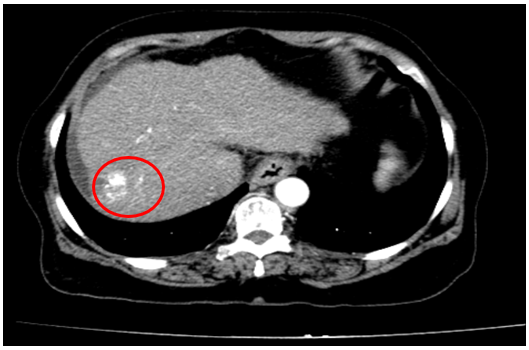

Tháng 12/2024

Chụp cắt lớp vi tính ổ bụng

Gan: Biến đổi hình thái, phì đại HPT I, bờ gan không đều. Nhu mô gan phải có khối giảm tỉ trọng kích thước 30x31mm, ranh giới không rõ, co kéo bao gan lân cận, tỷ trọng hỗn hợp, gồm phần tăng tỉ trọng của vật liệu nút mạch, phần tỷ trọng tổ chức vùng ngoại vi, sau tiêm ngấm thuốc mạnh thì động mạch, thải thuốc thì tĩnh mạch

Dịch quanh gan 22mm. Dịch tự do ổ bụng dày nhất 28mm

=>Hình ảnh u gan phải sau điều trị hiện còn phần ngấm thuốc sau tiêm (Vòng tròn đỏ), tăng nhẹ kích thước so với lần trước